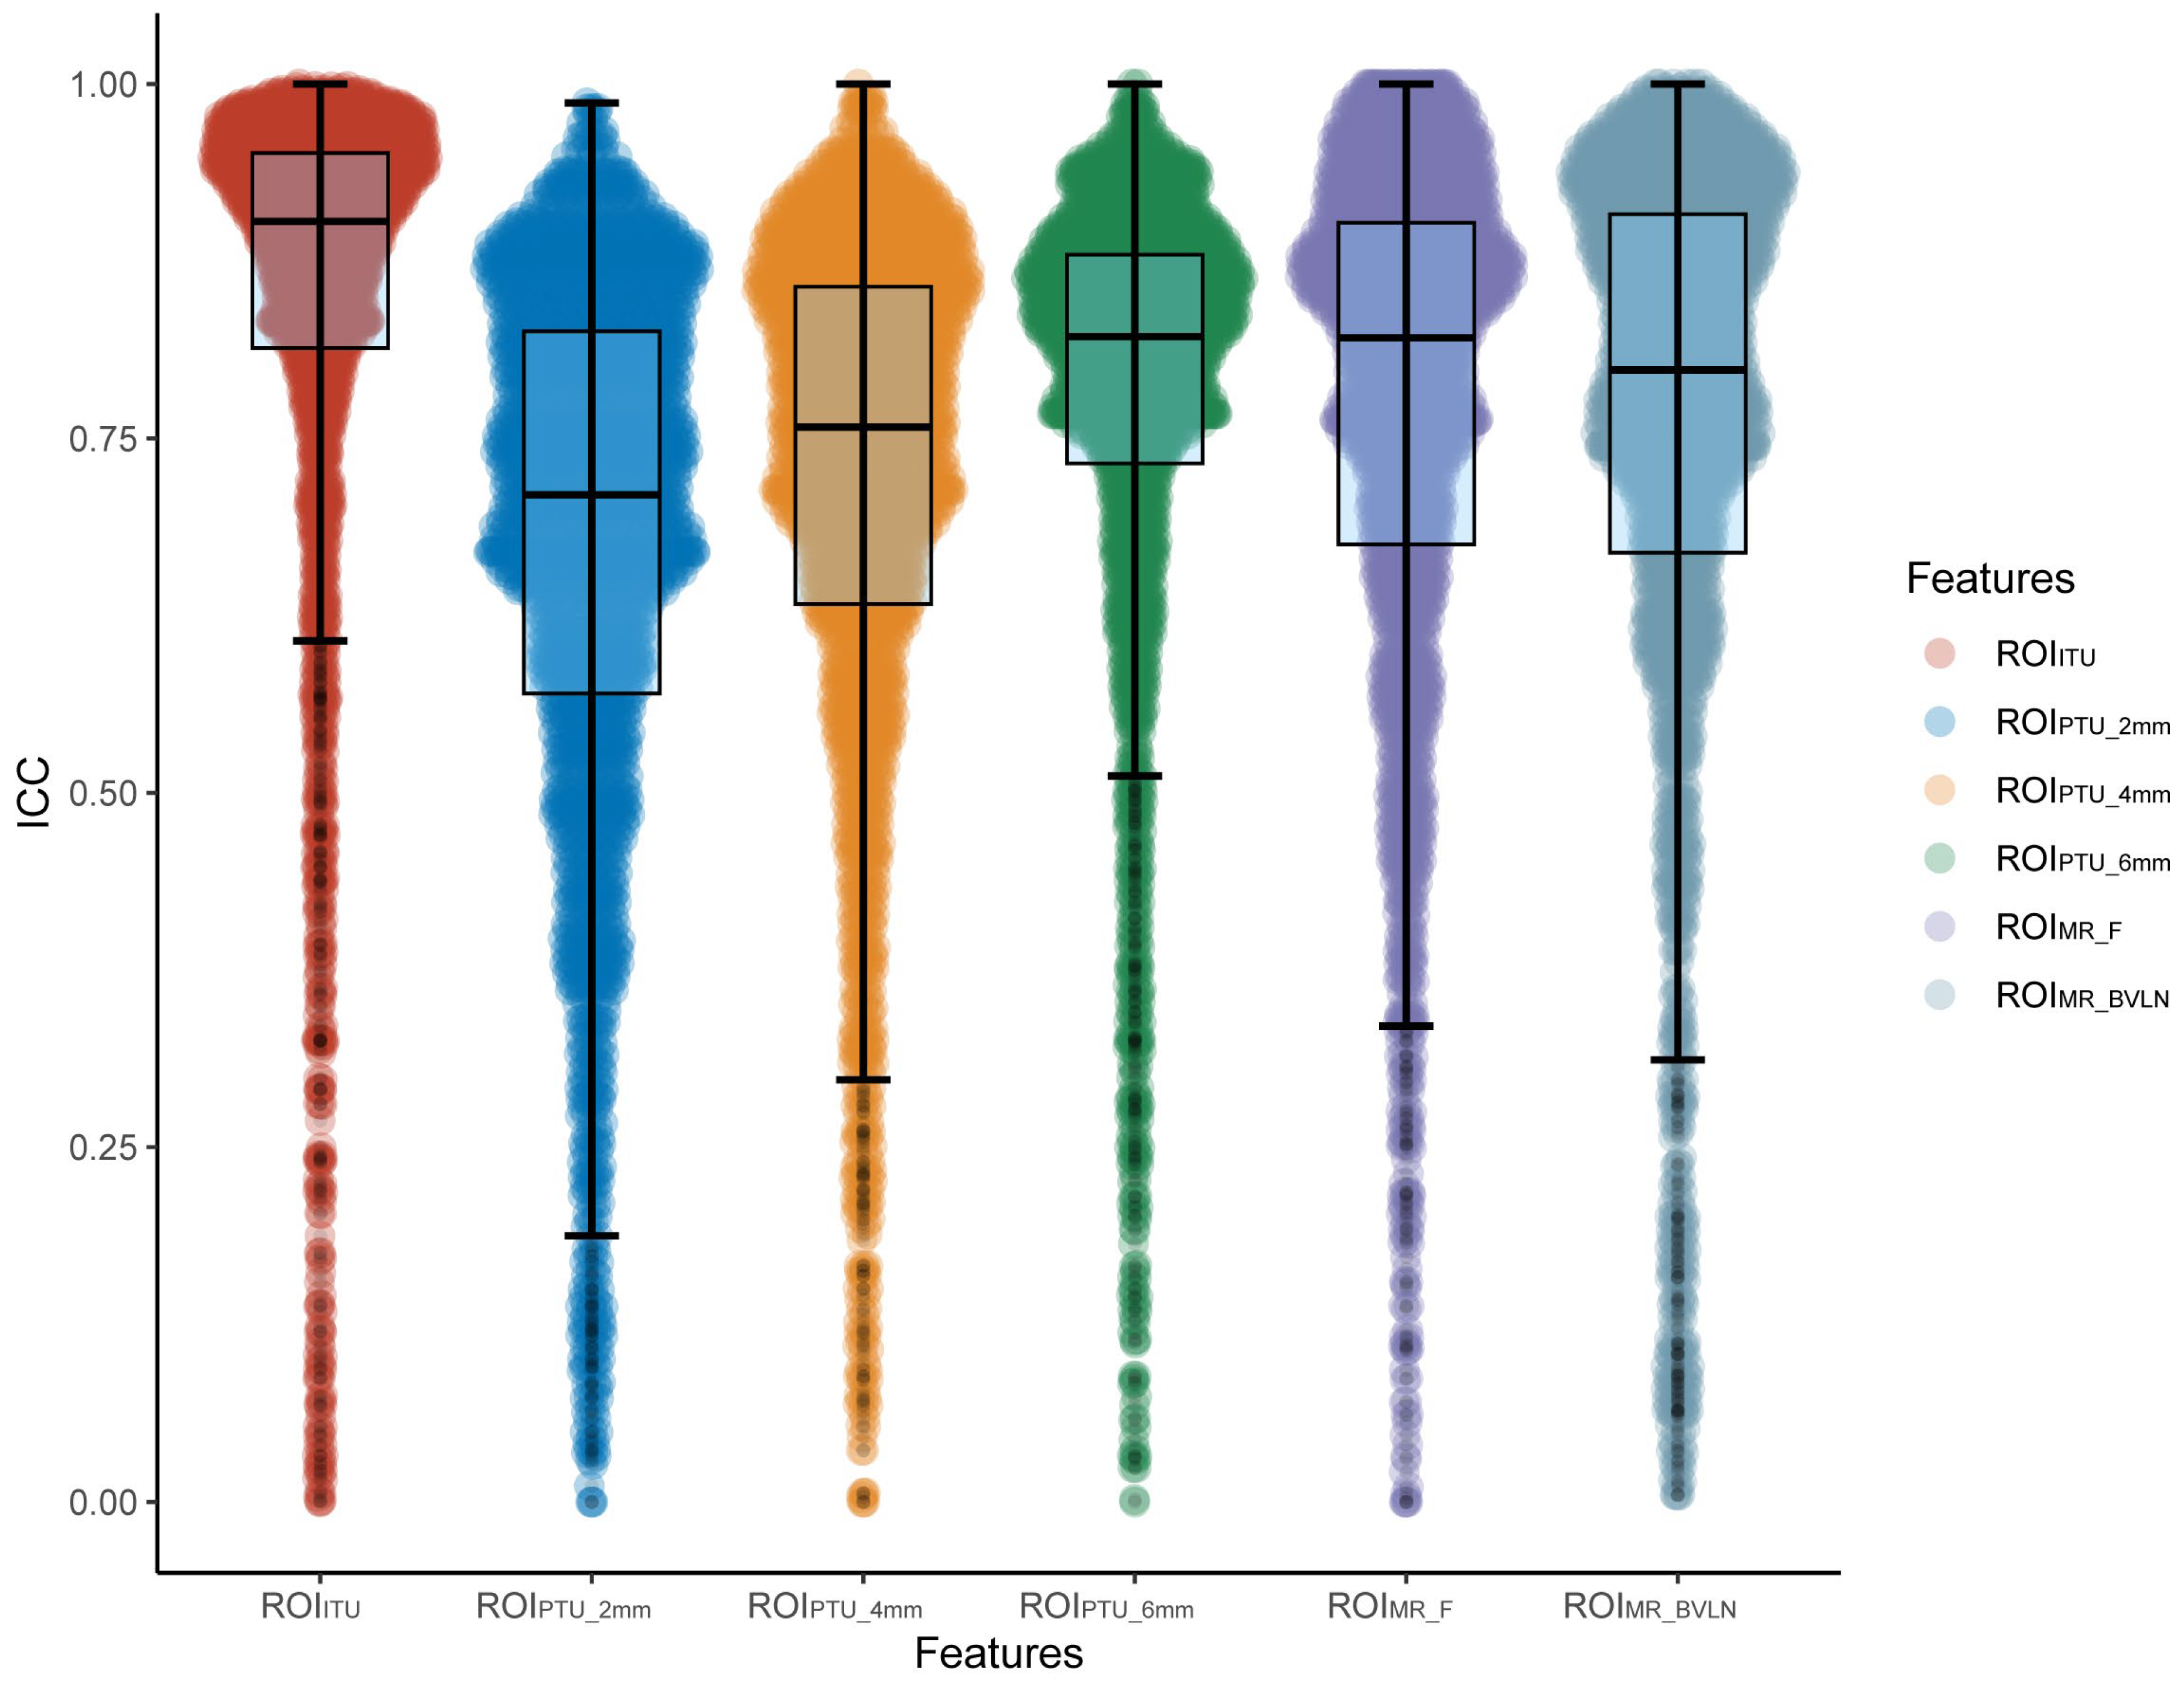

3.2. Feature Screening

3.3. Model Construction and Assessment